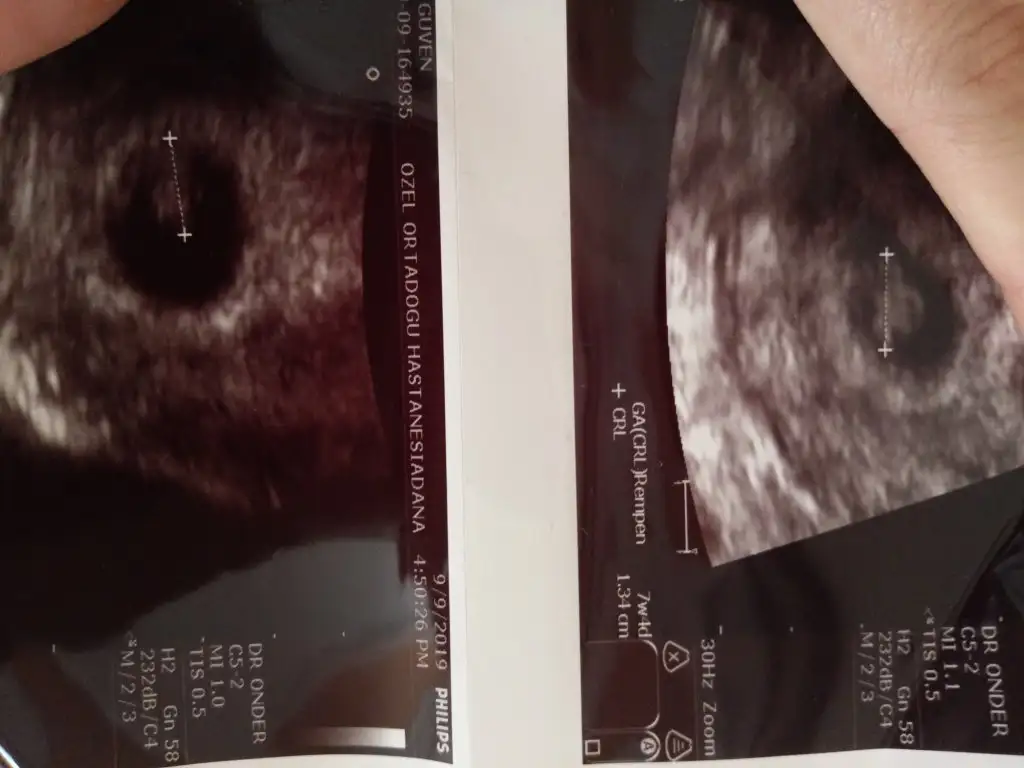

Burda da 7+4gunluk karından ultrason.iki oğlum var inşaallah niyetim kızim olması.oncelikle tabiki sağlıklı olmasi

• 1568802515683-309723974.webp

1568802515683-309723974.webp

24,8 KB · Görüntüleme: 52